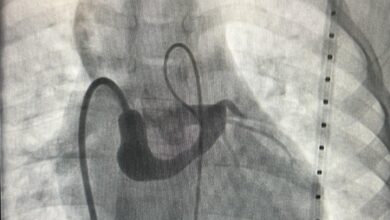

قسطرة قلبية لطفل في القصيم

أحوال – الأحساء – زهير بن جمعه الغزال: أنهى أطباء اختصاصيون في مركز الأمير سلطان لطب وجراحة القلب عضو تجمع القصيم الصحي معاناة طفل يبلغ من العمر 5 أعوام ويزن…